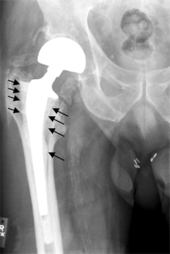

Bones with internal fixation devices in situ are at risk of periprosthetic fractures at the end of the implant, an area of relative mechanical stress. Post-operative femoral fractures are graded by the Vancouver classification.

Osteolysis

Many long-term problems with hip replacements are the result of osteolysis. This is the loss of bone caused by the body's reaction to polyethylene wear debris, fine bits of plastic that come off the cup liner over time. An inflammatory process causes bone resorption that may lead to subsequent loosening of the hip implants and even fractures in the bone around the implants. In an attempt to eliminate the generation of wear particles, ceramic bearing surfaces are being used in the hope that they will have less wear and less osteolysis with better long-term results. Metal cup liners joined with metal heads (metal-on-metal hip arthroplasty) were also developed for similar reasons. In the lab these show excellent wear characteristics and benefit from a different mode of lubrication. At the same time that these two bearing surfaces were being developed, highly cross linked polyethylene plastic liners were also developed. The greater cross linking significantly reduces the amount of plastic wear debris given off over time. The newer ceramic and metal prostheses do not always have the long-term track record of established metal on poly bearings. Ceramic pieces can break leading to catastrophic failure. This occurs in about 2% of the implants placed. They may also cause an audible, high pitched squeaking noise with activity. Metal-on-metal arthroplasty releases metal debris into the body raising concerns about the potential dangers of these accumulating over time. Highly cross linked polyethylene is not as strong as regular polyethylene. These plastic liners can crack or break free of the metal shell that holds them.